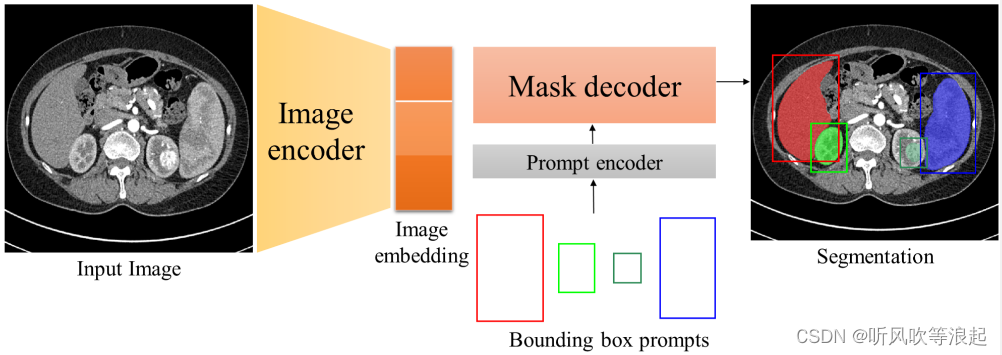

MedSAM 大模型利用了prompt engineering(提示工程)对指定区域进行分割

常见的分割提示有提示语、点、边界框等等,任务要求是收到提示符时至少输出一个有效的mask,哪怕提示是有歧义的

SAM通用分割大模型结构分为三个:图像编码器、提示器(prompt)和轻量级的解码器

这里的image encoder 输入size是1024*1024

因为SAM模型需要提示工程,所以传参的时候,也需要指定。这里是边界框,默认给定了。如果想要检测其他区域,需要更改这个bbox到自己想要推理的区域

本人之前一直在想,MedSAM有了bbox提示框后,怎么确认输入和输出的,其实通过dataset就可以知道

对于bbox提示边界框,也很简单,对前景取值即可,取x,y最小、最大,加个修正偏移即可

bbox在数据上的表现就类似于画框,将图像指定区域框出来,所以输入的维度就多加了1

这里有个疑问,为什么对于医学的灰度图像,要repeat成3通道呢?

要不然输入应该是2,而非4了